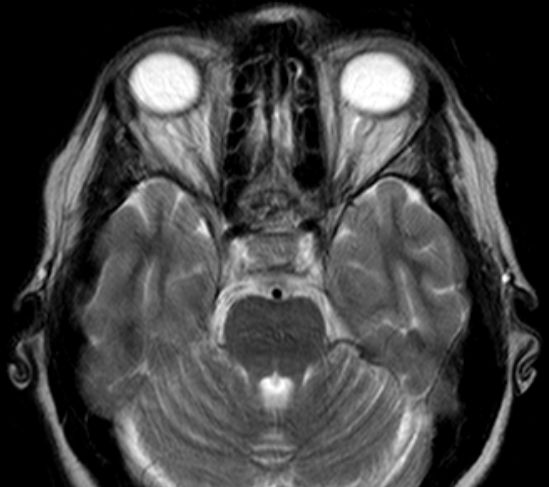

50-jährige Frau (I251), die vor 7 Jahre ein Mammakarzinom (rechts oben außen, T1c No Mo, invasiv NST hatte. Bisher metastasenfrei. Jetzt vor der Sella, in der linken Keilbeinhöhle eine z.T. verkalkte Raumforderung. 2 Jahre unverändert kontrolliert.